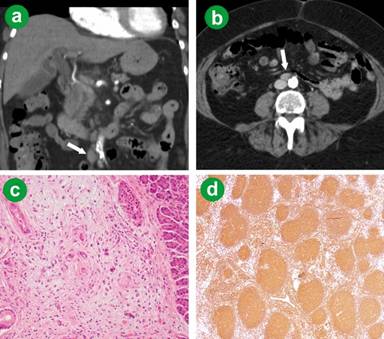

A 70-year-old lady with several months of general lethargy, intermittent nausea and vomiting had abdominal computed tomography (CT) showing a large mass within the duodenum and associated bile duct dilatation. Pre-operative tumour markers were unremarkable. Endoscopy showed a large tumour arising from the ampulla causing partial obstruction of the duodenum. Aorto-caval and retro-portal lymphadenopathy was noted on imaging (Figure 1ab). Positron emission tomography (PET) scan showed no obvious metastatic disease but a lesion in the right colon. At the time of surgery a large ampullary mass causing partial gastric outlet obstruction was noted as well as a mass in the caecum. A few indiscrete lesions were removed from the liver that on frozen section were not typical of malignancy. A classic pancreaticoduodenectomy with retroperitoneal lymph node dissection and right hemicolectomy was performed. Final pathology showed concurrent ampullary tubulovillous adenoma and pancreatic invasive intra-papillary mucinous neoplasia (IPMN) (Figure 1c) and a dysplastic colonic adenoma. There was no evidence of lymph node metastases, although several enlarged nodes were noted to contain grade 2 follicular lymphoma (Figure 1d). One of the liver lesions on permanent sections was consistent with metastatic pancreatic adenocarcinoma. Post-operative lactate dehydrogenase level (LDH) was normal. The patient had post-operative gemcitabine based chemotherapy and is tumour free on CT imaging 12 months following surgery. No treatment was given for the lymphoma due to the patient’s lack of symptoms.

Figure 1. a. Aorto-caval lymph node enlargement clear noted (arrow). Biliary dilatation by an ampullary mass is also observed. b. Cross sectional images further demonstrate enlarged aorto-caval lymph nodes (arrow). c. Focus of invasive ductal adenocarcinoma associated with intraductal papillary mucinous neoplasm (H&E x400) d. Lymph node, follicular lymphoma. Immunohistochemical stain for CD20 showing back to back follicles composed of CD20 positive B-cells (x40). |